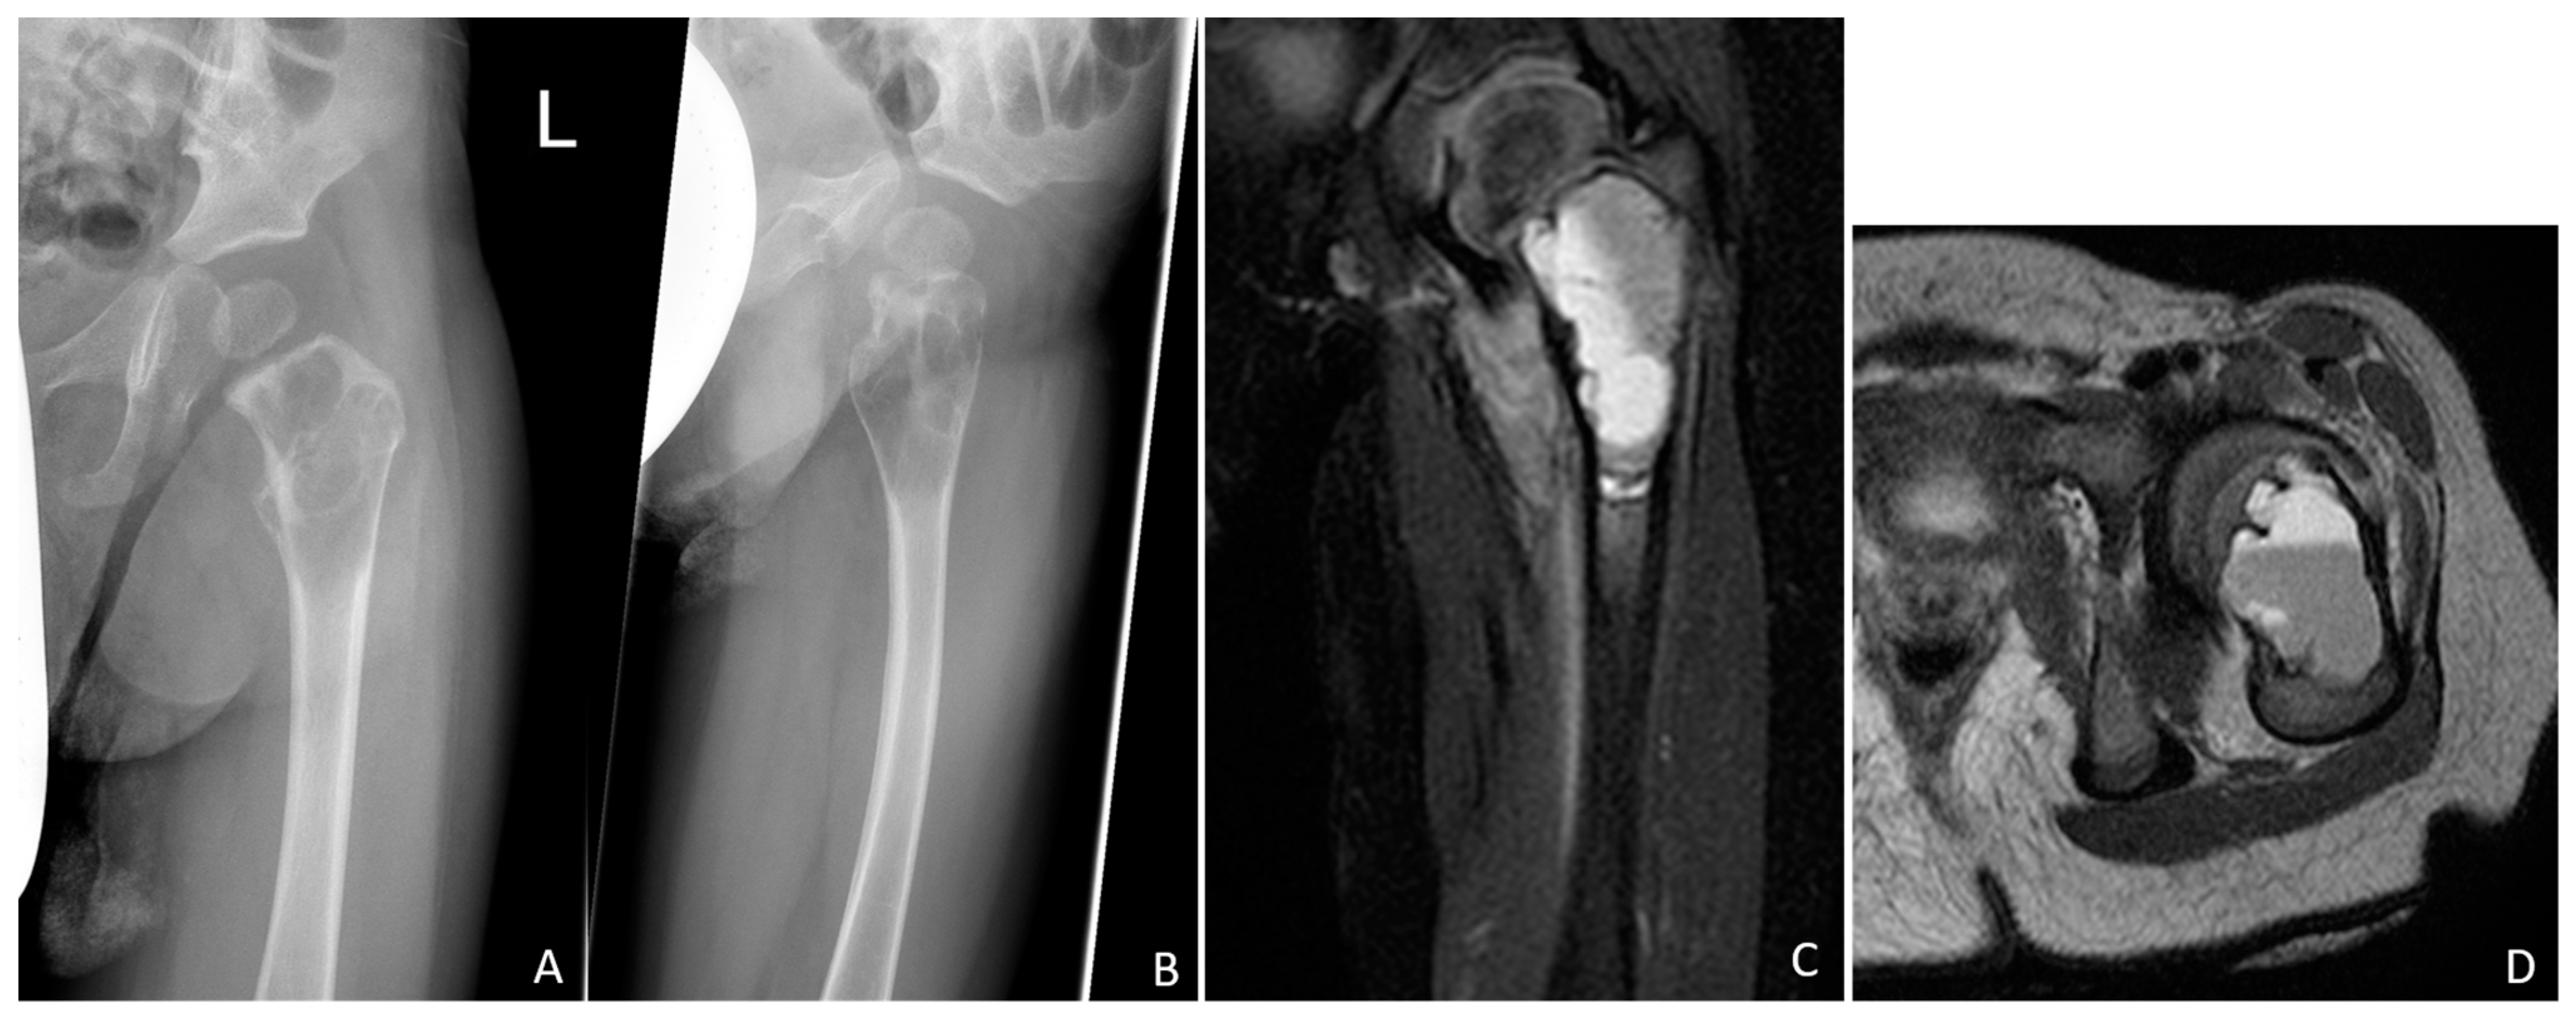

A 20-month-old boy presented with a limping gait pattern and sparing of the left leg. Radiological examination revealed osteolysis of the femoral neck and proximal femur, adjacent to the growth plate, with a typical multiseptated aspect, marked cortical weakening, or interruption in the axial image. Magnetic resonance imaging (MRI) clearly revealed the mirror formation of the cyst contents (Figure 1).

Figure 1.

Conventional radiographs of the left hip joint showing the septated cystic lesion of the proximal femur extending immediately to the growth plate in two planes (A,B). Perforation of the thinned cortical bone is indicated in the lateral image (B). The magnetic resonance image clearly shows the multichambered fluid-filled cyst, which is confined to the proximal femur (C,D). In the axial section, the fluid levels are clearly visible (D).